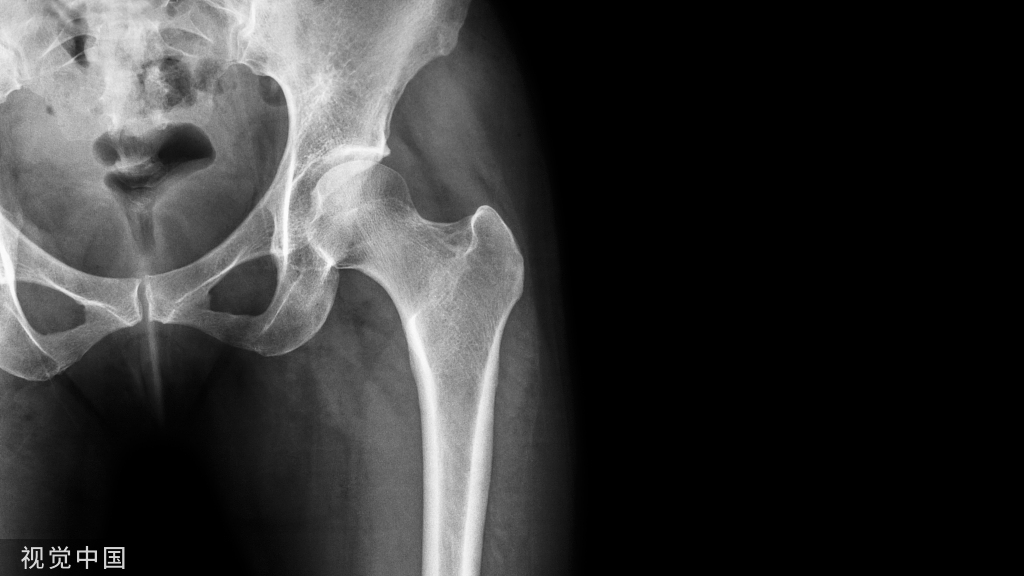

综上所述,进口和国产骨科内固定装置各有优缺点。在选择时,医生应根据患者的经济状况、年龄等具体情况和需求进行评估。同时,患者也应在医生的指导下做出决策,以确保获得最佳的治疗效果。